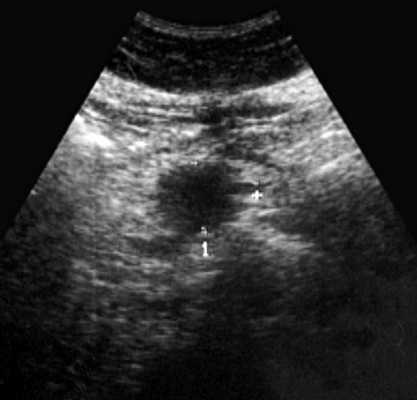

При УЗИ органов брюшной полости: печень в размере не увеличена (4,3-13,3 см), контур ее ровный, паренхима с умеренно выраженными явлениями жировой инфильтрации. Очаговой патологии не выявлено. Внутрипеченочные желчные протоки и вены, портальная (0,9 см) и селезеночная (0,4 см) вены не расширены. Холедох визуализируется фрагментарно, диаметр не превышает 0,8 см. Желчный пузырь не визуализируется (оперативно удален). Поджелудочная железа нормальных размеров (2,9-1,6-2,1 см), контур ровный, равномерно диффузно уплотнена. Вирсунгов проток не расширен. Диаметр сечения пищеварительного тракта на уровне пищеводного отверстия диафрагмы 1,6 см. В желудке натощак много слизи, стенка его не утолщена (0,3-0,5 см). На уровне наружного контура головки поджелудочной железы визуализируется округлой формы с ровными контурами пониженной эхогенности образование с нежной внутренней структурой размером 2,1x3,2 см (рис. 1). При полипозиционном исследовании выявить связь данного образования с головкой железы не удалось. В то же время, локально, на уровне данного образования толщина стенки дистального отдела луковицы двенадцатиперстной кишки составила 0,5 см (в остальных отделах 0,2-0,3 см). Селезенка не увеличена, структура ее однородная. Свободная жидкость в брюшной полости не определяется. Брюшной отдел аорты нормального диаметра (1,8 см). Парааортальные лимфатические узлы не визуализируются. Заключение: состояние после холецистэктомии. УЗ-признаки стеатоза печени, грыжи пищеводного отверстия диафрагмы. Киста головки поджелудочной железы? Для исключения патологии желудка и двенадцатиперстной кишки показано проведение рентгенологического и эндоскопического исследований.

Рис. 1. Эхограмма дивертикула двенадцатиперстной кишки, симулировавшего кисту поджелудочной железы.

Рассматриваемый случай интересен тем, что большой дивертикул двенадцатиперстной кишки при ультразвуковом исследовании симулировал кисту поджелудочной железы. Кисты (псевдокисты) поджелудочной железы встречаются значительно чаще дивертикулов, поэтому вполне естественно заключение о наличии у больной кисты. Однако отсутствие указаний в анамнезе на острый или хронический панкреатит, неудачная попытка проследить связь выявленного жидкостного образования с головкой поджелудочной железы при полипозиционном исследовании, локальное утолщение дуоденальной стенки позволили высказать предположение о возможной прочей патологии и назначить дообследование.